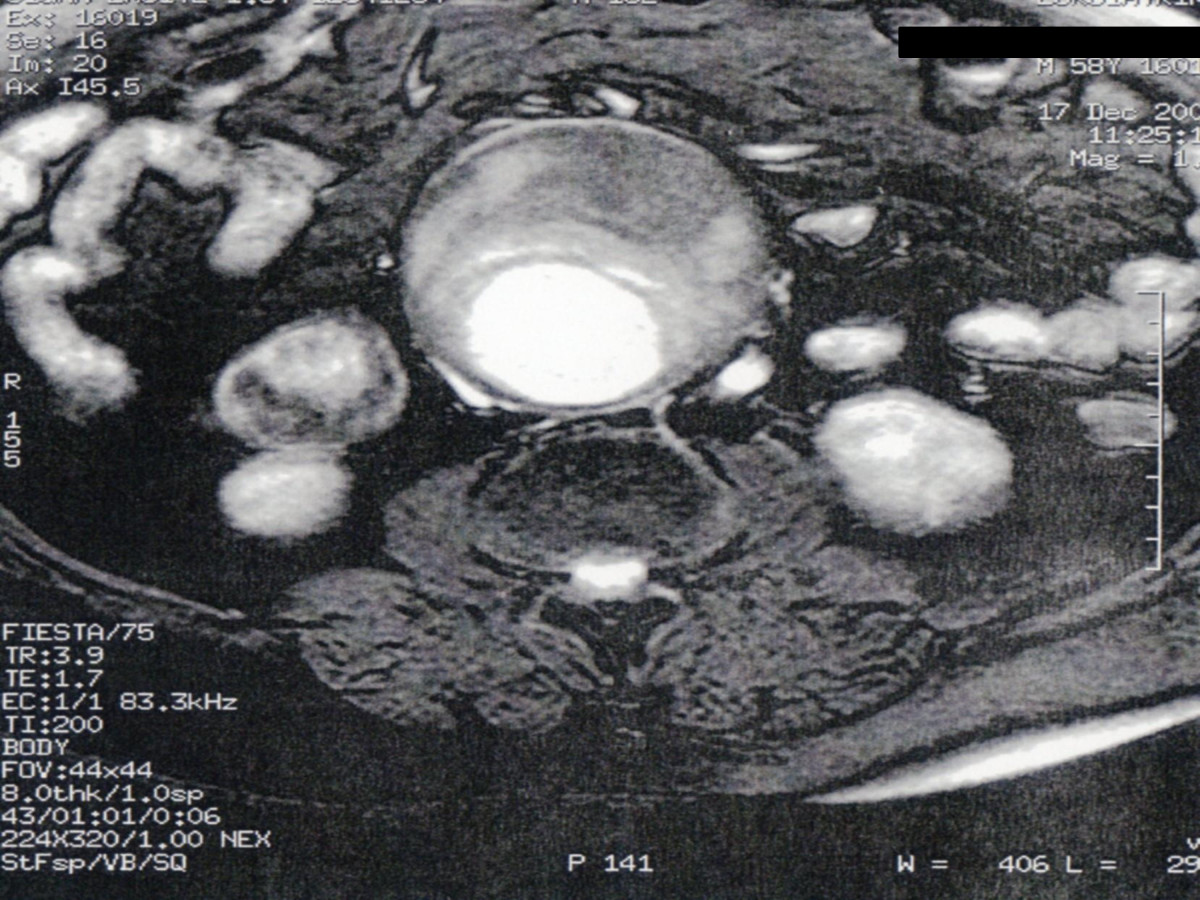

Ενδαγγειακή αποκατάσταση ανευρυσμάτων κοιλιακής αορτής

12ο Πανελλήνιο Συνέδριο Αγγειακής και Ενδαγγειακής Χειρουργικής

2010, Αθήνα